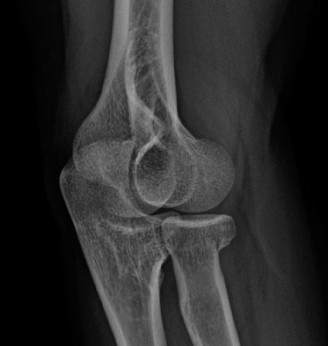

It should be noted that reverse total shoulder arthroplasty is also the procedure of choice in patients with cuff-tear arthropathy (aka rotator cuff arthropathy). Characteristics of cuff-tear arthropathy include superior migration of the humerus due to a massive rotator cuff tear, glenohumeral joint destruction, subchondral osteoporosis, and humeral head collapse (see Fig. 2–17). A reverse total shoulder

Figure 2–17_X-rays of a patient showing evidence of cuff tear arthropathy. The humerus is migrated superiorly, the glenohumeral joint is destroyed, there is subchondral osteoporosis, and the humeral head is collapsed. (From Ecklund KJ, Lee TQ, Tibone J, Gupta R. Rotator cuff tear arthropathy. _J Am Acad Orthop Surg. 2007;15(6):340–349.)